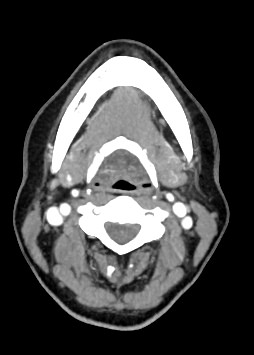

В компьютерном томографе излучатель рентгеновских лучей установлен в кольцевой части аппарата и, непрерывно вращаясь вокруг зоны исследования, производит послойное сканирование в различных плоскостях. В результате получаются снимки анатомической зоны в мельчайших подробностях, а после цифровой обработки полученных данных – точные трехмерные объемные модели исследуемой области. При этом изображения органов можно приблизить, повернуть в разные стороны, что значительно повышает точность диагностики различных заболеваний.

Для улучшения визуализации мягкотканных структур (внутренних органов, клетчаточных пространств, связок, мышц, сухожилий, кровеносных сосудов и лимфатических узлов) в ряде случаев проводится дополнительно контрастное усиление. Для этого пациенту внутривенно вводится йодсодержащий контрастный препарат, который активно поглощает рентгеновские лучи. Благодаря способности контраста накапливаться в патологических участках, они становятся хорошо видны на снимках КТ. Контрастное усиление позволяет оценить состояние сосудистой системы, выявить участки воспаления и опухолевые образования. С помощью контрастирования удается выявлять опухоли минимальных размеров, определить точные размеры и границы опухоли, степень ее воздействия на окружающие ткани.